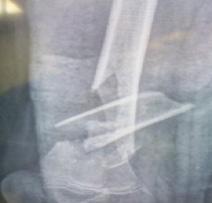

Manejo ortopédico de la artropatía hemofílica en México. Por: Dr. Armando R. Hernández Salgado, Ortopedista y Traumatólogo, Cirujano de Artroscopia y Cirugía de Rodilla, Especialista en Artropatía Hemofílica, Asesor Voluntario de FHRM. Pág. 109